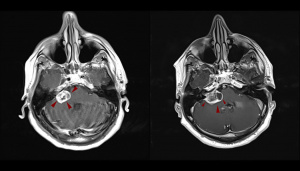

ΑΚΟΥΣΤΙΚΟ ΝΕΥΡΙΝΩΜΑ ΜΕΤΑ ΑΠΟ ΘΕΡΑΠΕΙΑ ΜΕ CYBERKNIFE – 3 & 9 MHNEΣ “ΜΕΤΕΓΧΕΙΡΗΤΙΚΑ”

Η θεραπεία ολοκληρώνεται συνήθως σε μία ημέρα και χρησιμοποιείται συχνά για μικρούς όγκους εγκεφάλου, μεταστάσεις και ακουστικά νευρινώματα.

Το CyberKnife αποτελεί ένα σύγχρονο σύστημα ακτινοχειρουργικής που χρησιμοποιεί γραμμικό επιταχυντή ακτίνων Χ υψηλής ενέργειας. Η ακτινοβολία κατευθύνεται μέσω ενός ρομποτικού βραχίονα από πολλές διαφορετικές γωνίες προς τον στόχο.

Το CyberKnife χρησιμοποιείται για όγκους εγκεφάλου, μεταστάσεις και βλάβες της σπονδυλικής στήλης. Το κόστος του CyberKnife διαμορφώνεται με βάση διάφορους παράγοντες, με βασικό τον αριθμό των συνεδριών.